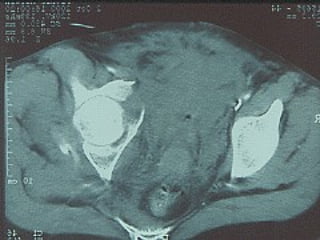

Tc pre op

TC RMN